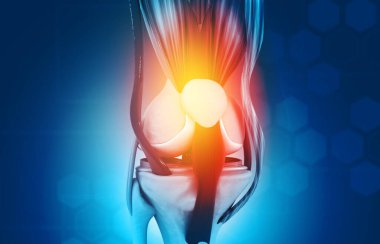

diz, anatomi, kemik

RenderkişiİnsanKadınerkekTıbbiAdamciltParmaklarKemikkolgövdebiyolojiOmuzGöğüsAcıDizkafatasıomurgaEklemKaburgaKalçaİskeletanatomiomurilikRADIUSx ışınıAğrıkadınlarKafesgörevleriçene kemiğiGöğüs kemiğiskapulaLeğen kemiğikarpalsakrumTibiaUyluk kemiğifibulaKöprücük kemiğipazı kemiğidirsek kemiğibasdiz kapağıkemiklerischiumdziewczynkiBenzer İçerikler